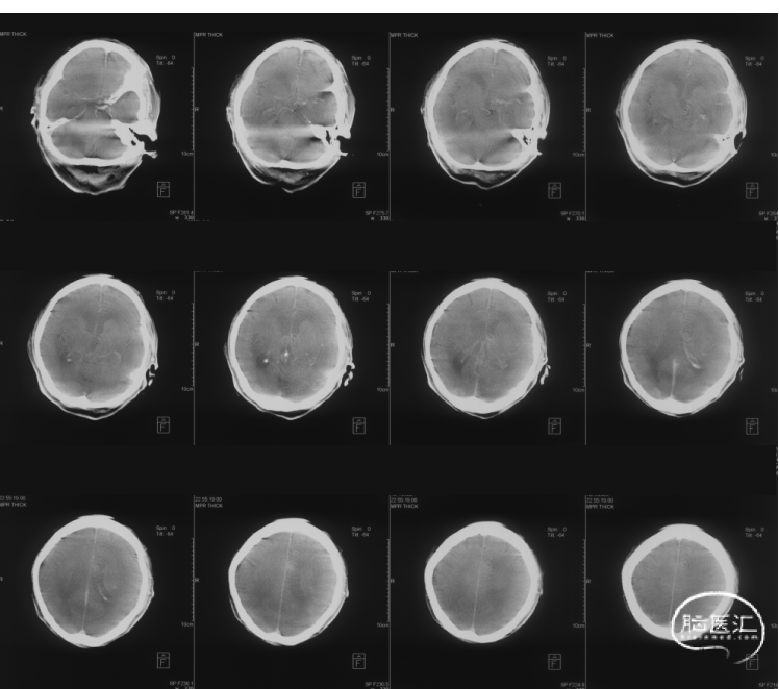

急诊影像学检查结果

(1)头颅CT:未见颅内出血,左侧颈内动脉末端-大脑中动脉血管走行区高密度征;ASPECTS评分7分。

(2)急诊头颅CTA、CTP:左侧颈内末端闭塞,前交通开放,右侧颈内动脉通过前交通动脉向左侧大脑前动脉代偿供血并逆向充盈至左侧大脑前动脉A1段(箭头所指)。灌注成像提示CBF<30% 15ml,Tmax>6s 168ml,mismatch 153ml。

术后情况:麻醉苏醒后,查体症状较前明显改善,NIHSS 6分。术后24h查体NIHSS 3分,复查头颅CT未见大面积梗死。患者为心源性栓塞,术后24h后给予利伐沙班15mg/日抗凝治疗。